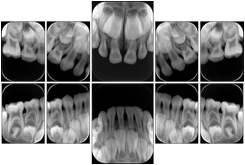

- OO-1. Intra-oral Full Mouth Series Structured Display